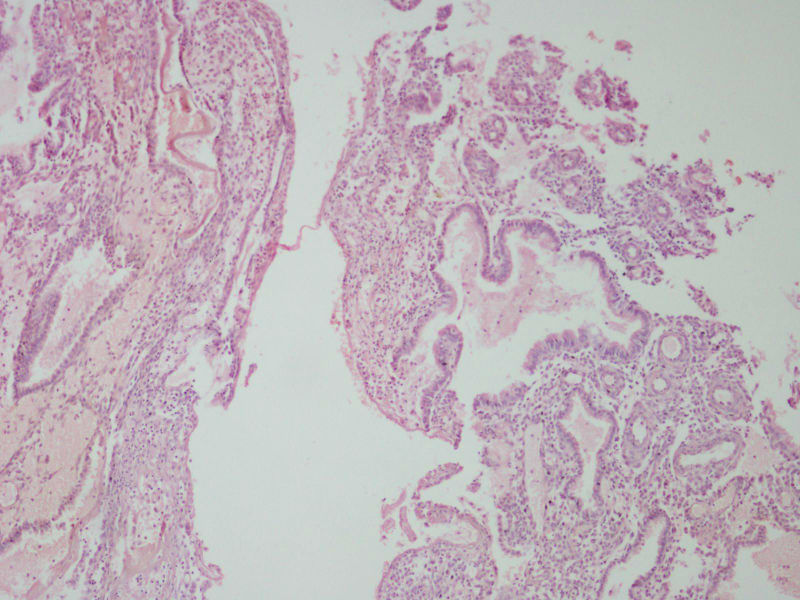

图1

女44,阴道不规则流血一月

流血期宫内膜